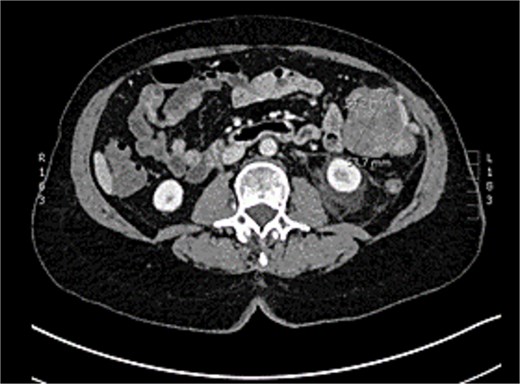

CT abdomen and pelvis was showed uncomplicated diverticulitis; however, a lobulated 54 × 54 mm exophytic mass arising from the transverse colon with adjacent enlarged lymph nodes was incidentally noted (Figs 1 and 2). Colonoscopy, limited by diverticulosis, found no intraluminal mass but revealed desmoplastic mucosal changes at the splenic flexure. Biopsies were nondiagnostic. Staging CT chest showed no metastases, and CEA was 4.0.

CT abomen + pelvis with contrast demonstrating ~5 × 5 cm exophytic lobulated mass at splenic flexure, appearing to arise from transverse colon.